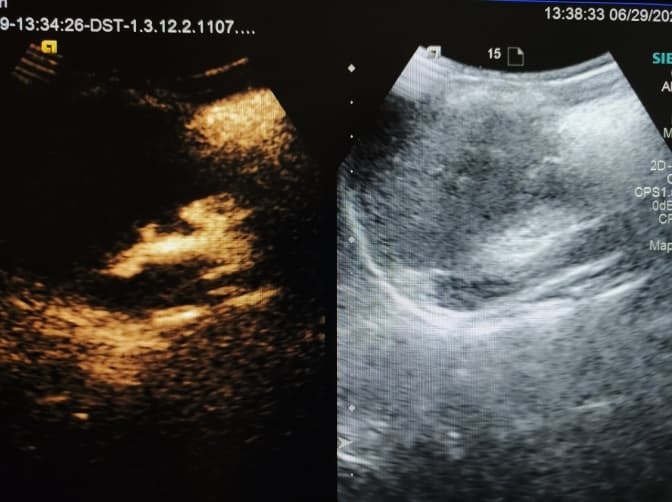

Урологи Західноукраїнського спеціалізованого дитячого медичного центру провели першу в Україні ультразвукову контрастно-підсилено мікційну цистографію. Дослідження допомогло підтвердити вроджену ваду сечовивідної системи у 5-річної дівчинки з Турківщини. Про це повідомили у пресслужбі лікарні.

Відтак, з допомогою УЗД-цистографії з контастним підсиленням вдалось підтвердити причину частих інфекцій – двобічний міхурово-сечовий рефлюкс. Тепер дівчинку чекає відповідне лікування в урологів лікарні, зауважують медики.

«Суттєвими перевагами ультразвукової мікційної цистографії є відсутність іонізуючої радіації, нешкідливі гіпоалергенні контрастні середники і більша, порівняно з рентгенівською, чутливість та специфічність в діагностиці порушень уродинаміки», – повідомив лікар променевої діагностики ЗУСДМЦ Віктор Жельов.

Зазначимо, що цистографія – високоінформативний метод дослідження, що дозволяє отримати зображення безпосередньо порожнини сечового міхура, а также шляхів його поширення - уретри і сечоводів та чашко-мискових комплексів. Завдяки цистографії можна діагностувати складні захворювання: сечовідний рефлюкс, пухлини, свищі, запальний процес та інші.